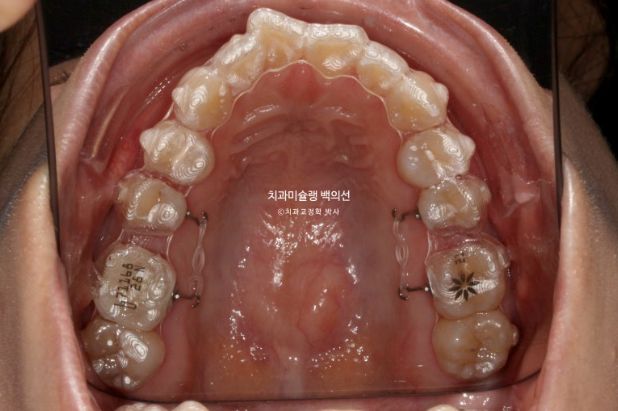

재제작 당시 모습입니다.

24.07

앞니 배열은 좋아졌고

큰어금니 발치공간은 많이 줄었으나

큰어금니 쓰러짐이 보입니다.